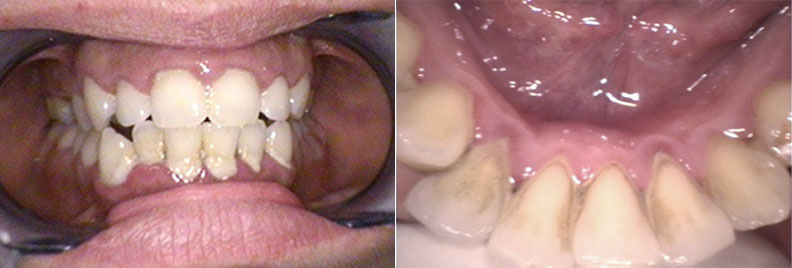

Periodontics

Periodontal disease, or gum disease, can cause significant damage to the soft tissue and bone supporting your teeth, potentially leading to tooth loss. Our periodontic treatments, including deep cleanings and scaling and root planing, are designed to halt the progression of gum disease, reduce inflammation, and restore the health of your gums.